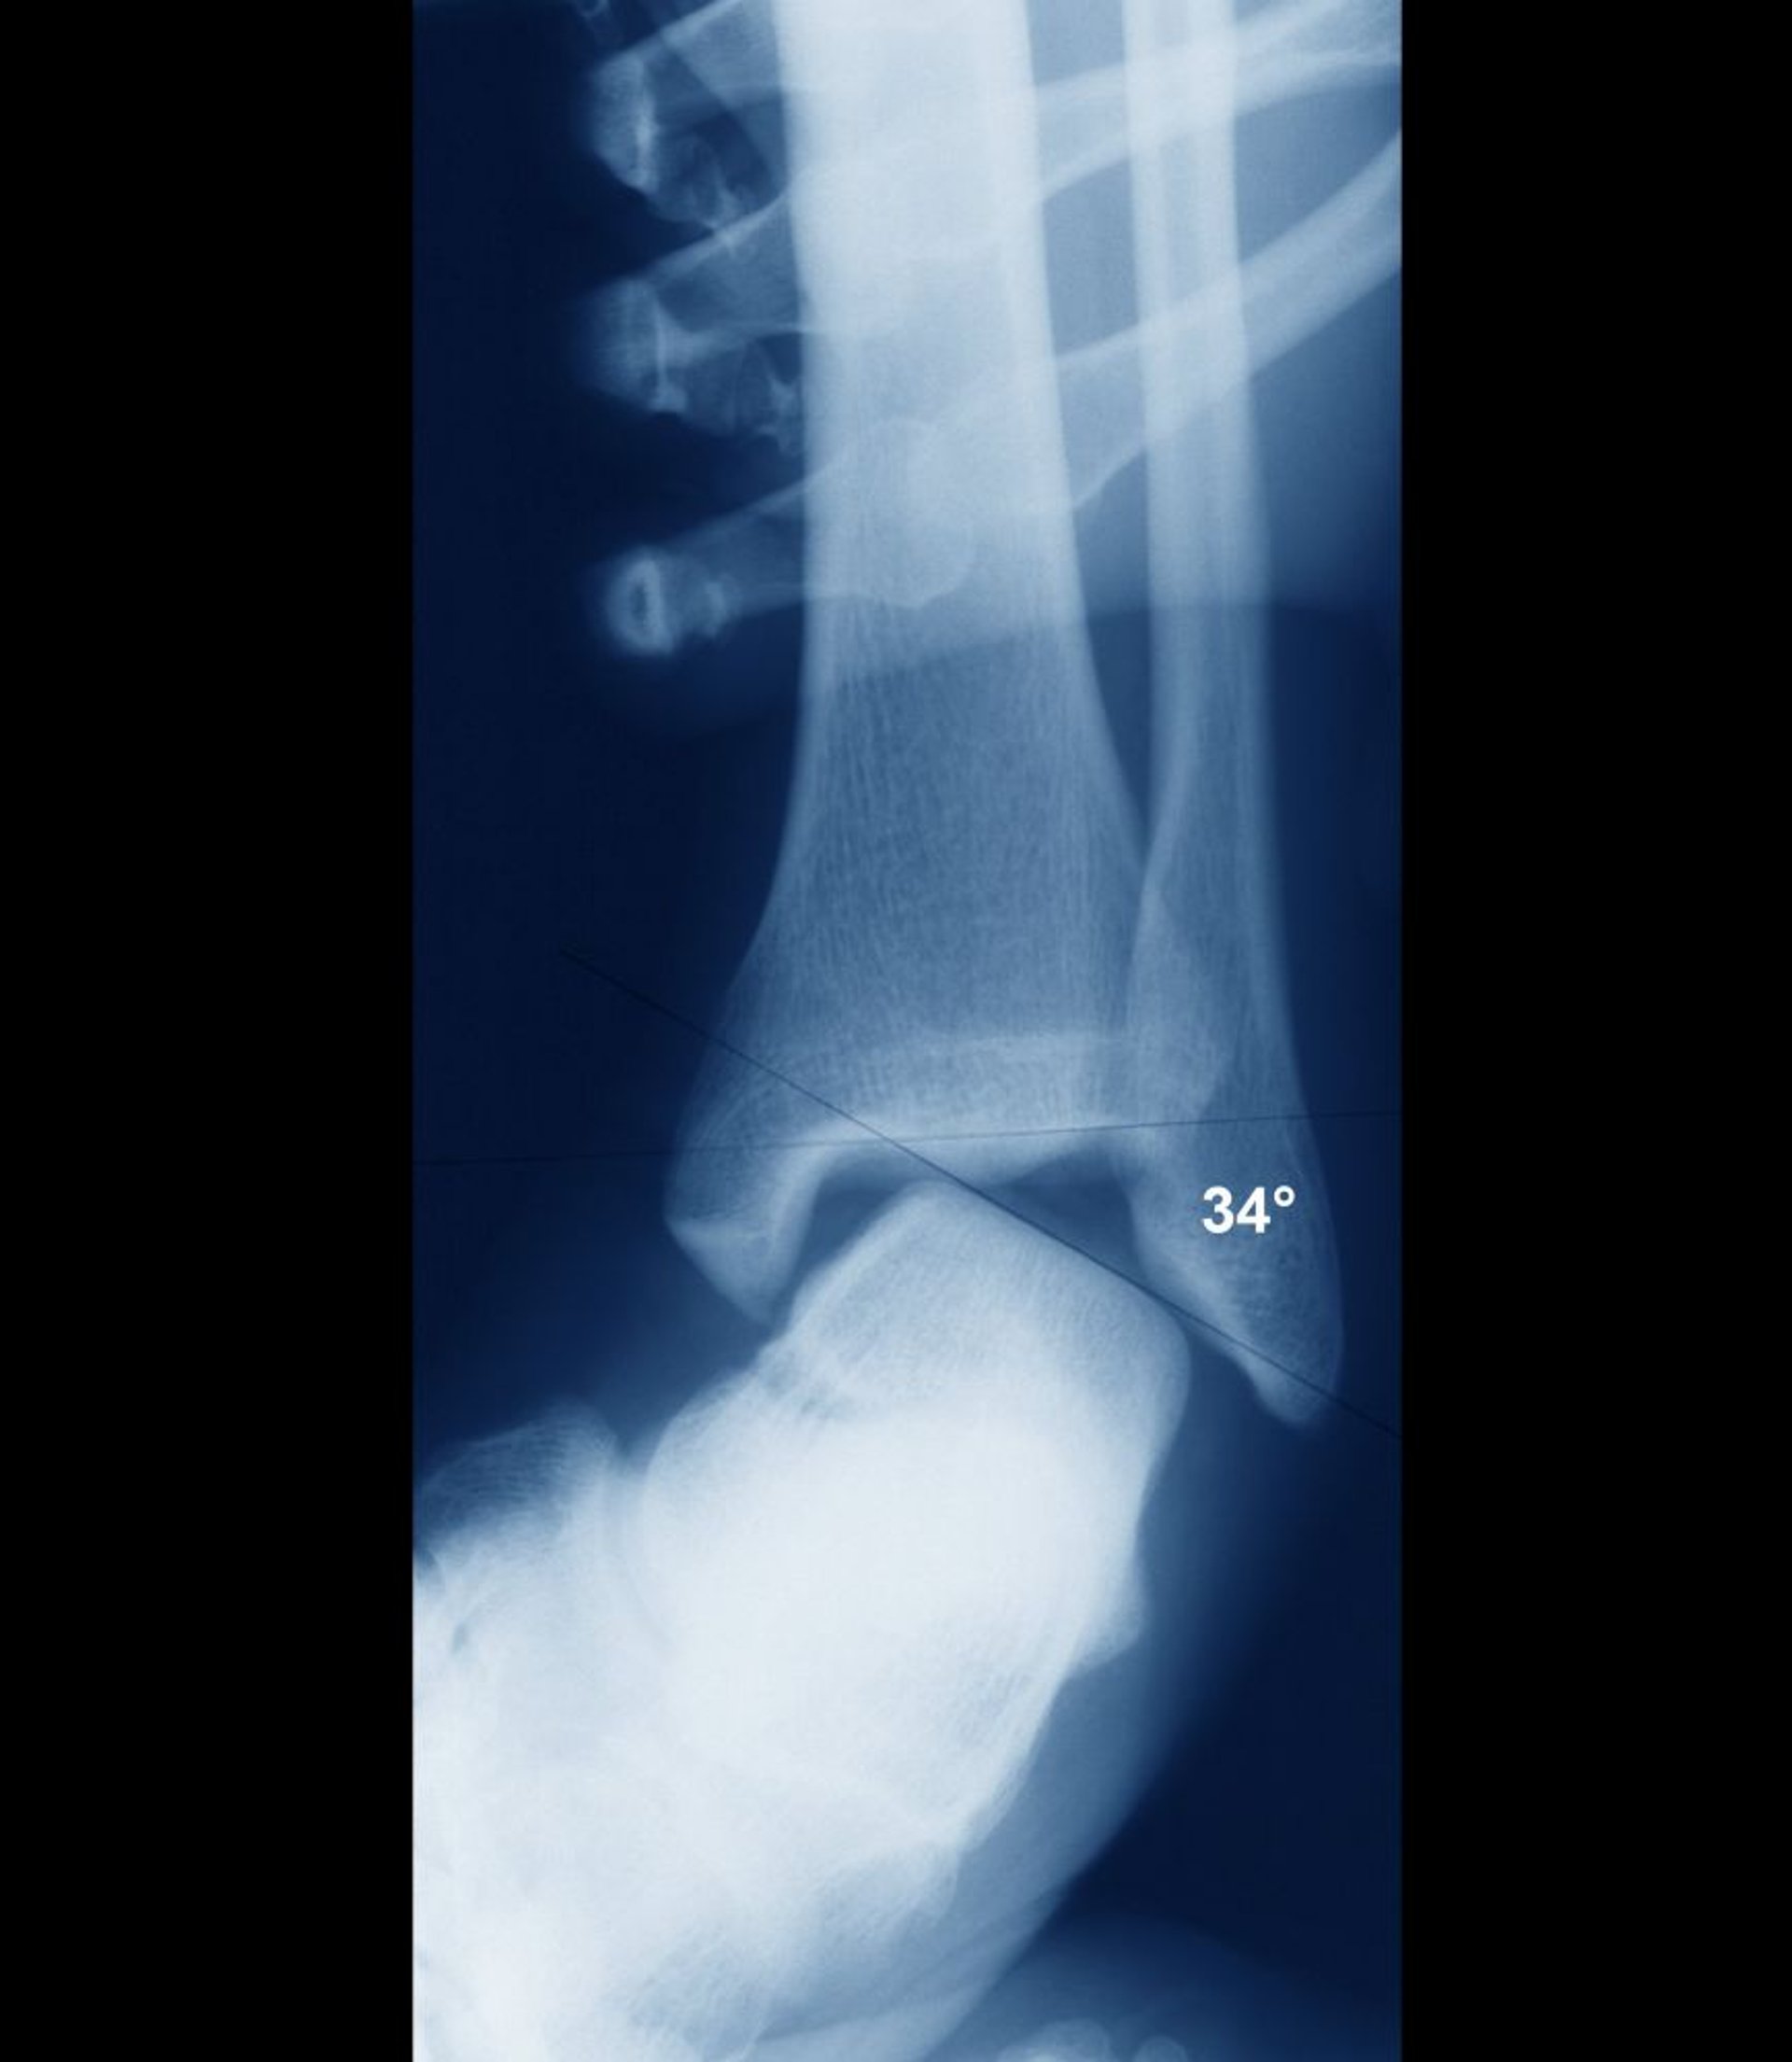

Distorsione alla caviglia con instabilità

Se la caviglia è stabile, le superfici intra-articolari dell'astragalo e della tibia devono essere parallele. Qui, sono ampiamente disallineati, indicando una grave instabilità articolare. L'instabilità sarebbe stata chiaramente evidente clinicamente e l'instabilità è normalmente valutata clinicamente senza bisogno di raggi x.